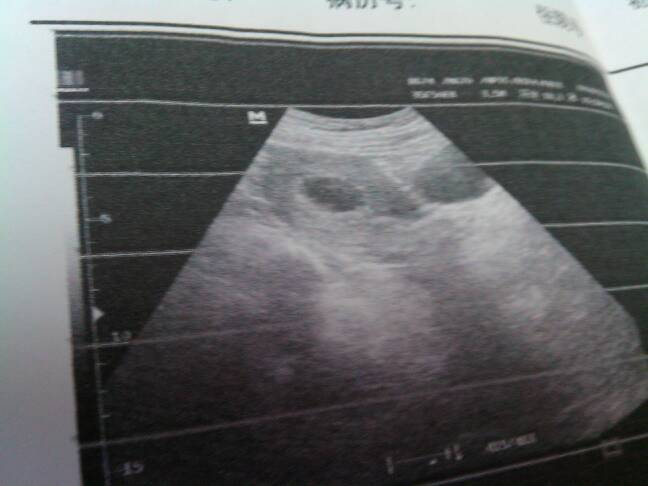

今天去做了彩超,,医生说这时间段,,没有胎牙,,是怎么回事,,怎么又和上次怀孕一样了,呜呜呜呜,让我在等一个星期,还去检查,